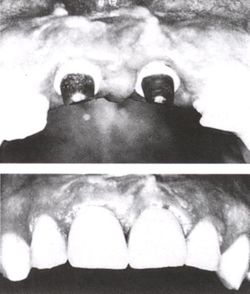

Mouth with many implant supported teeth where it is difficult to distinguish the real teeth from the prosthetic teeth.

Individual teeth were replaced with implants where it is difficult to distinguish the real teeth from the prosthetic teeth.